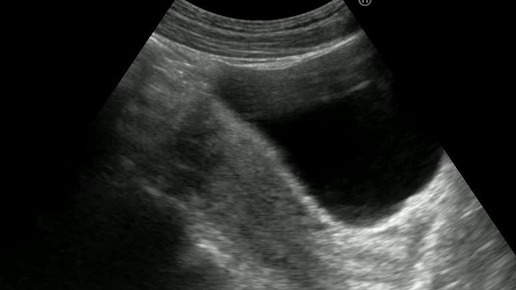

Видео к статье: "Свободная жидкость в брюшной полости"https://dzen.ru/a/Z-1KdOK-KyrjRiGF

Ультразвуковые находки от врача УЗД Зорина Я.П.